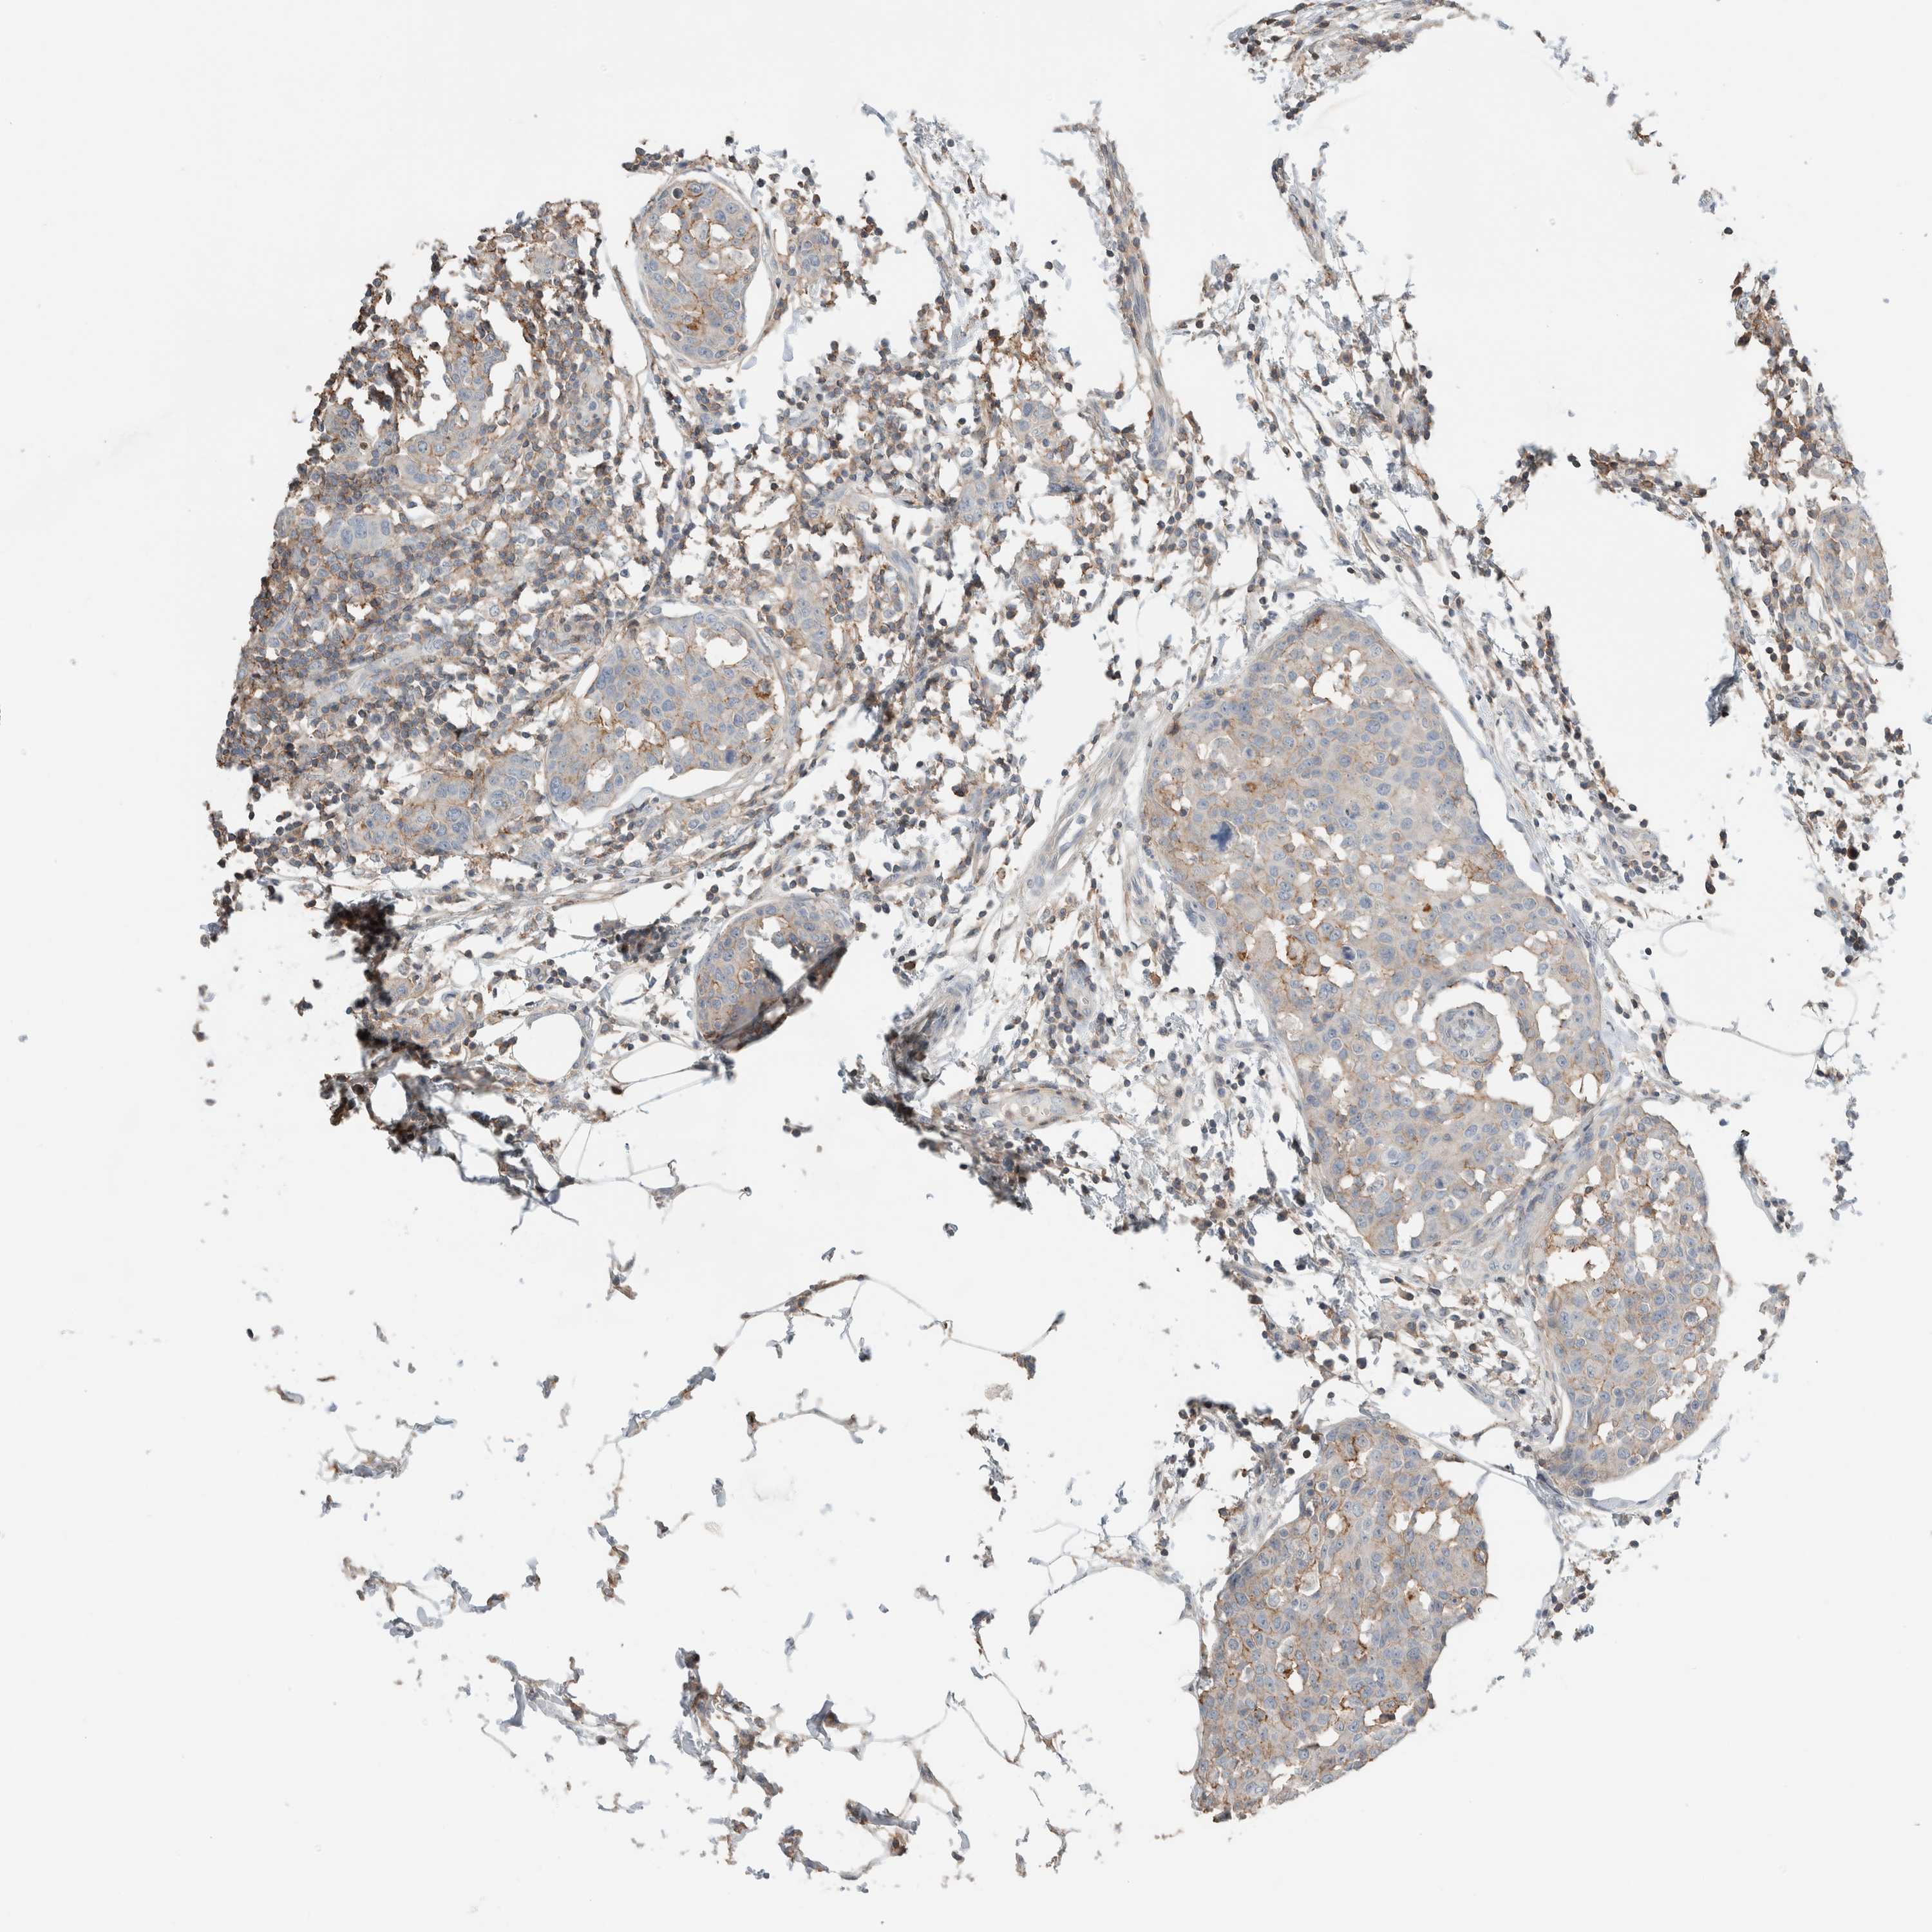

BRCA TCGA BRCA VALIDATION PROTEIN EXPRESSION